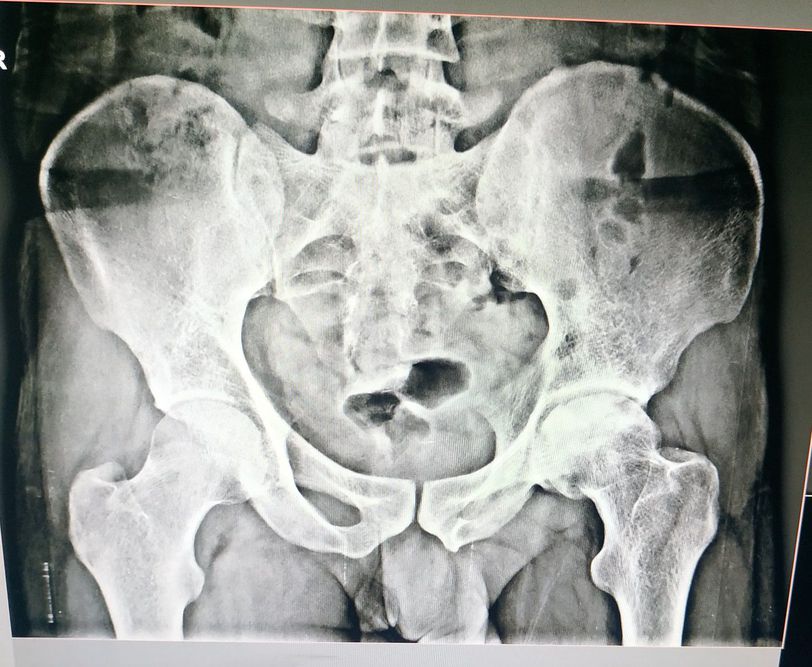

Pain in both knees and pelvic region What is the diagnose .....????

Left femoral head necrosis (AVN)

May be peripheral spondyloarthritis.

Is the pelvis slightly twisted? The right side looks anteriorly tilted and the left side looks posteriorly titled.